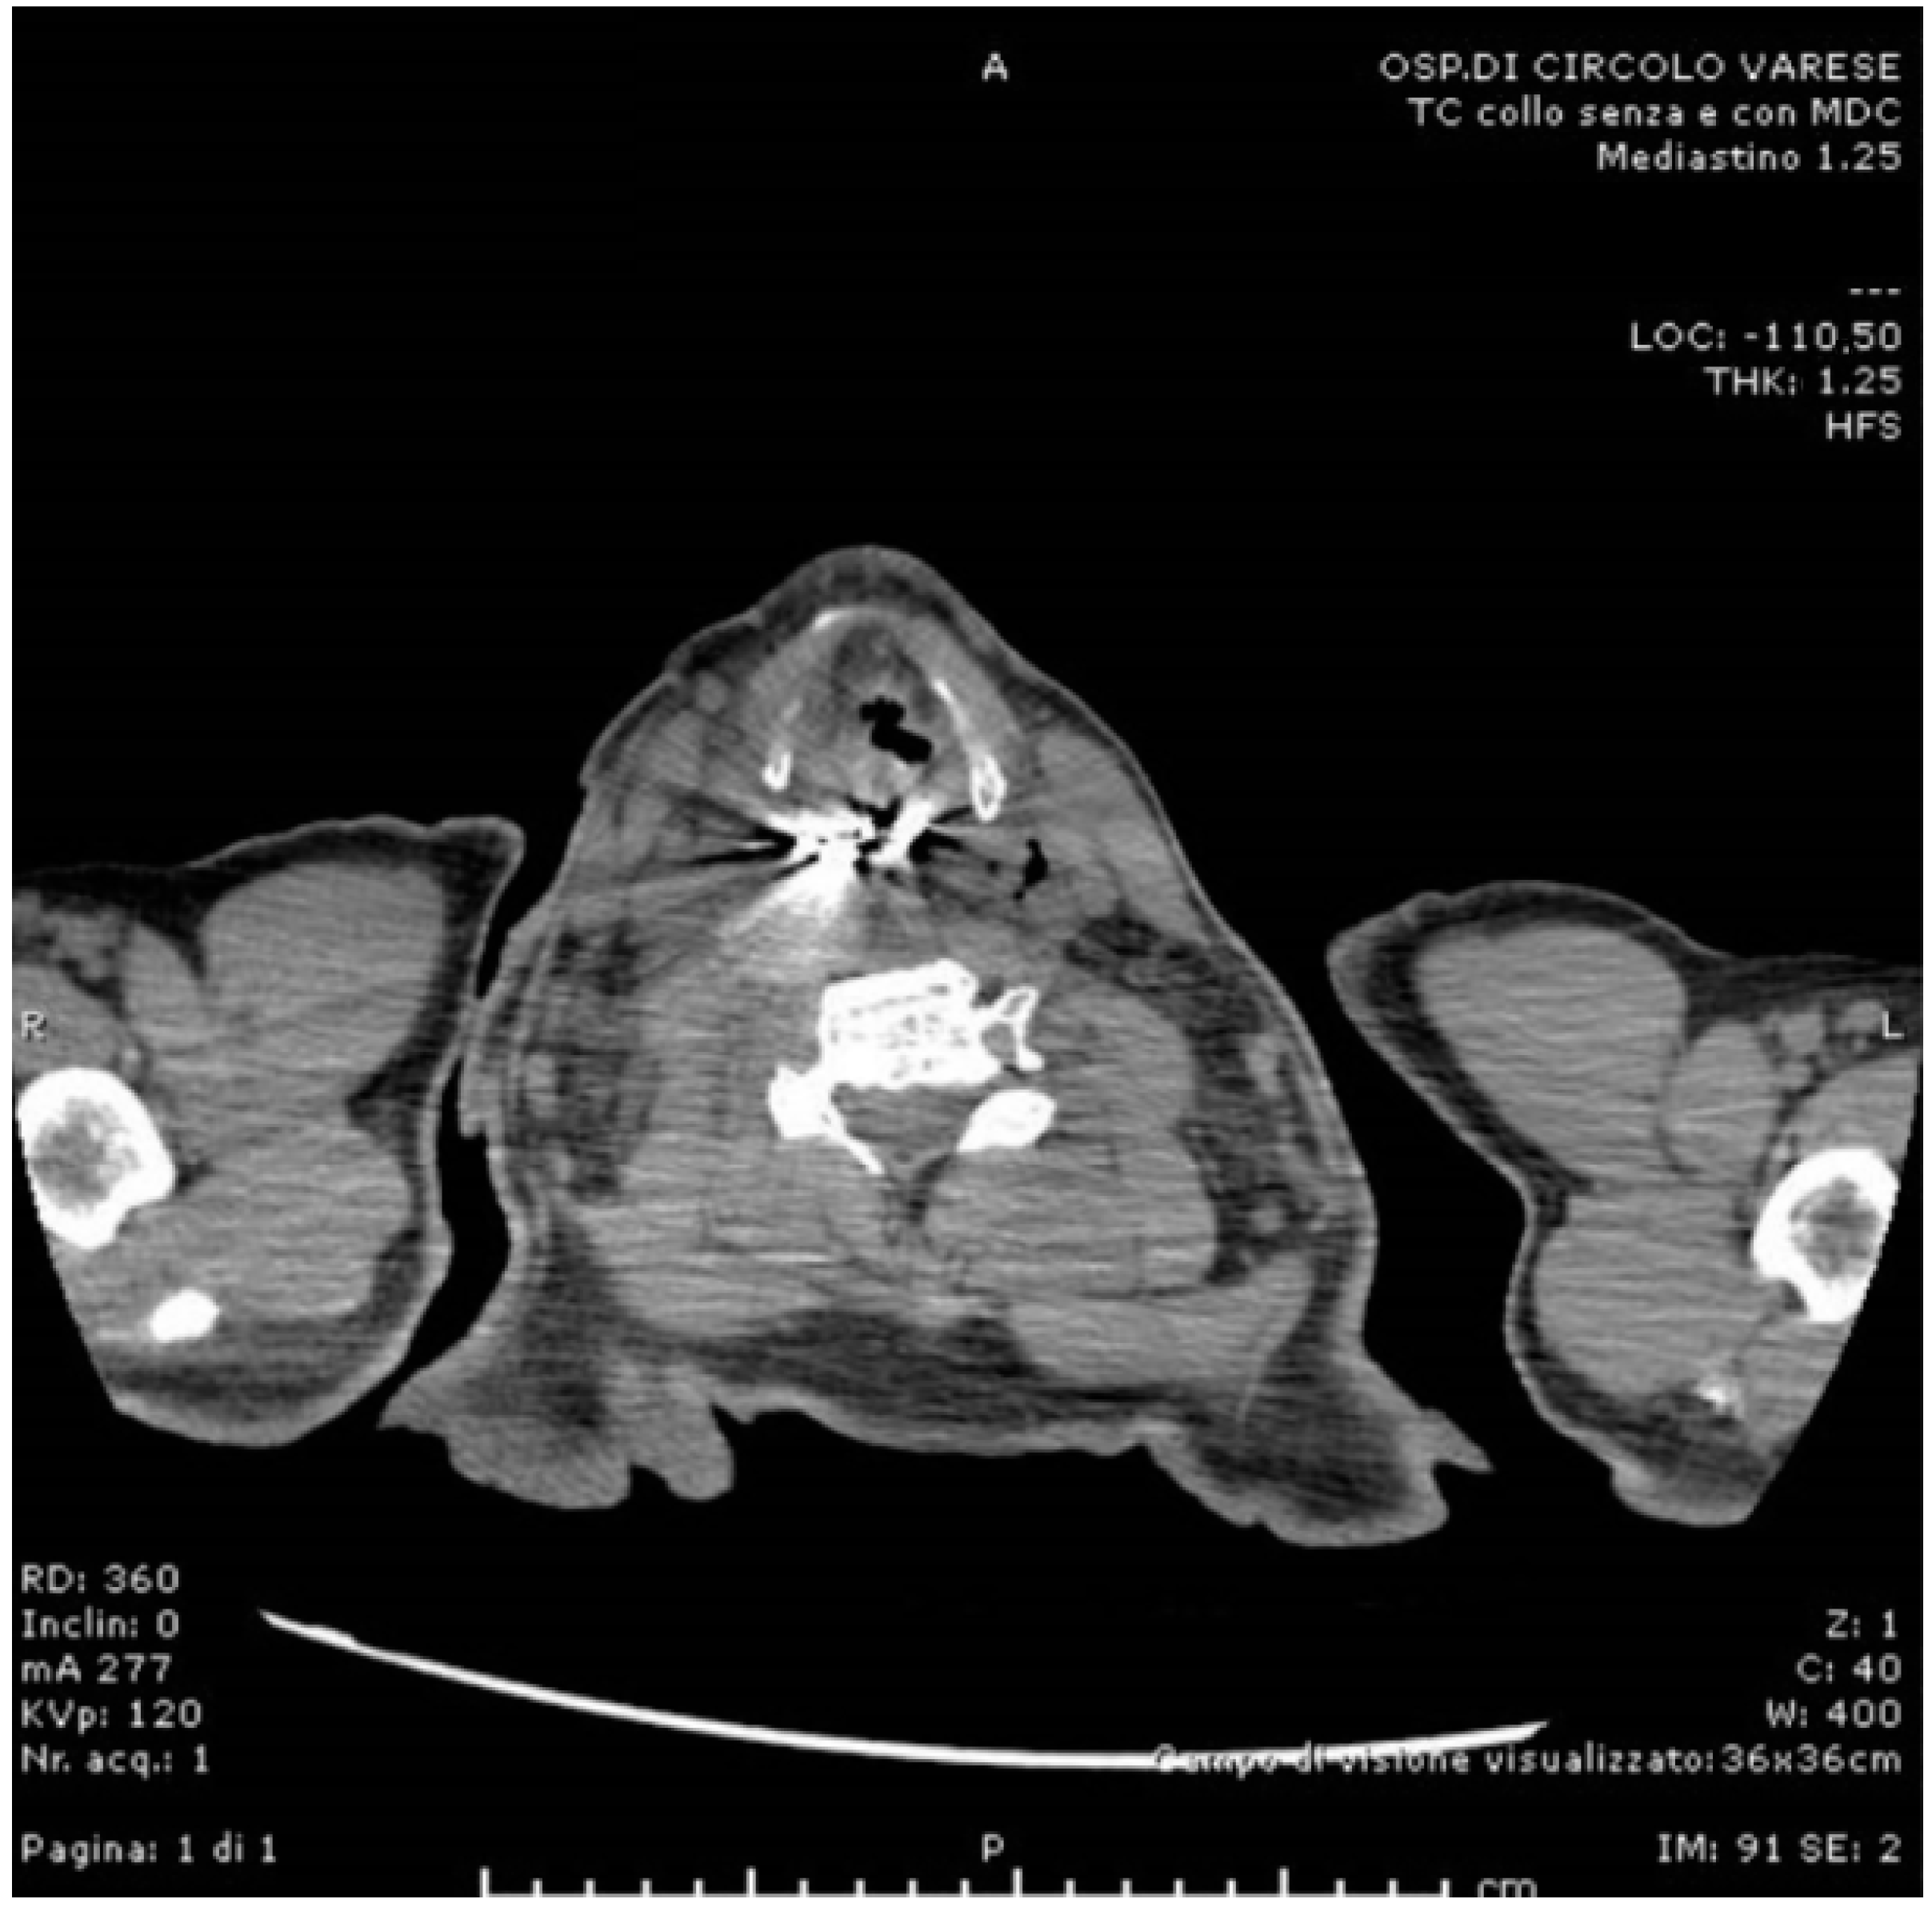

2. Case Presentation